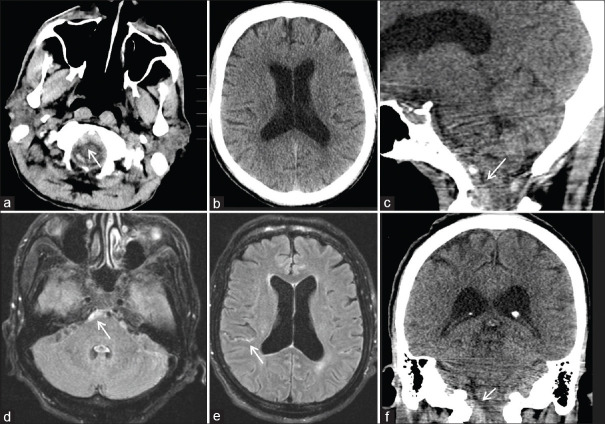

Spinal arachnoid web (AW) is a rare condition causing spinal cord-related issues. Its cause is often idiopathic but can be linked to past trauma or spine surgery. We describe two cases of AWs that developed after subarachnoid hemorrhage (SAH). Case #1 is a 71-year-old male with nonaneurysmal SAH who developed myelopathy 1 year later. Magnetic resonance imaging revealed upper thoracic cord edema and an AW. Case #2 is a 57-year-old female who underwent coiling of a ruptured basilar artery aneurysm and ventriculoperitoneal shunting for hydrocephalus. Twenty months later, she developed mid-thoracic AW requiring surgical resection. Both patients showed symptom improvement postresection avoiding further reoperation. History of SAH is emerging as a risk factor for AW development, emphasizing the importance of monitoring delayed-onset myelopathy and back pain in recent SAH patients.

脊髓蛛网膜(AW)是一种罕见的疾病,会引起脊髓相关问题。其病因通常是特发性的,但也可能与过去的创伤或脊柱手术有关。我们描述了两例在蛛网膜下腔出血(SAH)后出现的蛛网膜瘤。病例1是一名71岁的男性,患有非动脉瘤性SAH,1年后出现脊髓病变。磁共振成像显示上胸段脊髓水肿和 AW。病例 2 是一名 57 岁的女性,因脑积水接受了基底动脉瘤破裂的盘绕手术和脑室腹腔分流术。20 个月后,她患上了中胸 AW,需要进行手术切除。两名患者在切除术后症状均有所改善,避免了再次手术。SAH史正在成为AW发病的一个危险因素,这强调了监测近期SAH患者迟发性脊髓病和背痛的重要性。